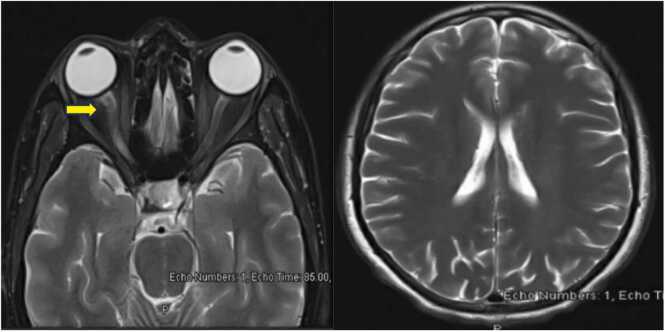

Lumbar Puncture and Cerebrospinal fluid (CSF) analysis were done to exclude viral CNS infection and possible other inflammatory conditions and showed WBC of 44/ul (Normal range 1–5/ul), 97 % lymphocytic, RBC 2/ul (Normal range 0–2/ul), Glucose 2.90 mmol/l (Normal range 2.22–3.89 mmol/l) and protein of 0.65 gm/l (Normal range of 0.15–0.45 gm/l). CSF was negative for culture and viral panel as well as oligoclonal bands. Her MRI brain and orbit MRI confirmed right optic neuritis. (Fig. 1 The patient was started on IV Methylprednisolone 1000 mg daily for five doses. She showed a slight improvement in her eyesight from nil to hand movement at a 50 cm distance on discharge. Follow up visits at one week and two months after discharge for the patient showed that her vision stabilized at “close counting fingers” level with no further improvement.

Fig. 1.

MRI Sections of the brain and orbit with contrast. The right optic nerve appears swollen with evidence of abnormal T2WI hyperintensity involving the chiasmatic, canalicular, and proximal to mid-orbital segments with mild blurring of the retro-orbital fat.(Arrowed).